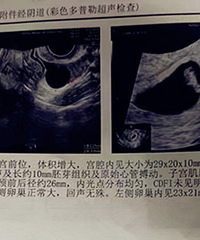

预产期:2022-6-13建卡医院:葭芷卫生院产检医院:葭芷卫生院、台州市第一人民医院胎宝宝小名:还没有取生产医院:目前打算是中心医院B超照片/孕期相关